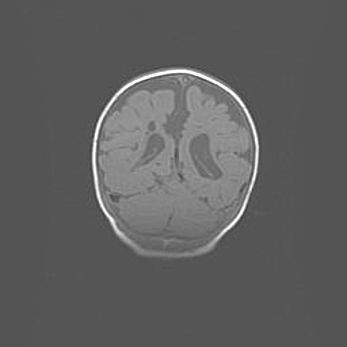

Наружная гидроцефалия с возможной атрофией височных областей.

Возраст: 28 дней

Вес: 3670 г

Пол: мужской

Окружность головы: 38 см

Срок гестации: 40 недель

Гидроцефалия головного мозга у новорожденных – это заболевание, которое характеризуется скоплением избыточного количества спинномозговой жидкости в желудочковой системе головного мозга в результате затруднения её перемещения от места выработки к месту поглощения в кровеносную систему или вследствие нарушения абсорбции. При открытой наружной форме гидроцефалии у новорожденных расширяются и переполняются субарахноидные пространства.

При нормотензивных  формах,  которые,  как  правило,  являются  следствием  перенесенных ишемических  повреждений  паренхимы  мозга,  возможно  сочетание микроцефалии  с нормотензивной гидроцефалией. В основе данных изменений лежит атрофия больших полушарий с преимущественной  локализацией  в  лобно-височных  областях.